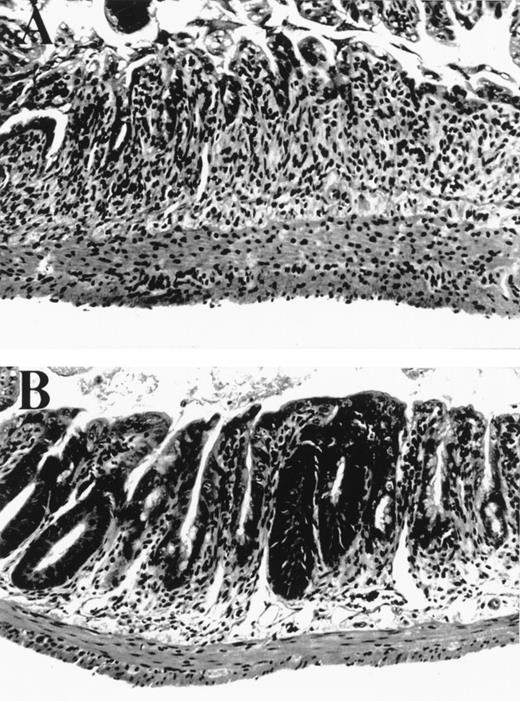

Small bowel histology 5 days after BMT. (A) Allogeneic control mouse, exhibiting severe villus blunting, extensive crypt destruction with no appreciable regenerative response, and a moderate lamina propria inflammatory infiltrate. (B) Allogeneic mouse treated with KGF from day -3 to +5 exhibiting moderate villus blunting, prominent crypt regenerative features, and minimal lamina propria inflammatory infiltrate. Features in syngeneic control mice (not shown) were identical to those in KGF allogeneic animals.

We tested the effects of KGF in a well established murine BMT system where GVHD is induced by both minor and major histocompatibility antigens (B6→ B6D2F1). We hypothesized that KGF may protect the GI tract epithelium from damage inflicted by cellular and inflammatory cytokine effectors of GVHD that occur in addition to that from radiation and chemotherapy. BMT recipients were conditioned with 1,550 cGy of TBI and transplanted with 2 × 106splenic T cells and 5 × 106 bone marrow cells from B6 (allo) or B6D2F1 (syn) mice. KGF was given to allogeneic BMT recipients from day -3 to day +5 at a dose 5 mg/kg/day subcutaneously. The severity of GI histopathology was examined on day 5 after BMT, a time of maximal GI damage in this model, according to a standard scoring system.15 Macroscopic evaluation of control-treated allogeneic recipients showed dilated and edematous bowel, while the intestine in both syngeneic and KGF-treated allogeneic mice appeared normal (data not shown). Microscopically, the small bowel in allogeneic BMT controls was more severely damaged than in syngeneic controls, with significant differences in several features of mucosal architecture and epithelial cytology (Table 1). The large majority of these parameters was reduced by KGF treatment (Table 1 and Fig 1) to the level found in syngeneic BMT recipients, completely abrogating the damage specific to GVHD. Interestingly, KGF treatment given before BMT only did not significantly protect the GI tract from GVHD (Table 1). KGF administration from day -3 to +5 also significantly reduced damage to colonic mucosa in allogeneic animals as determined by semiquantitative scoring of histologic features, which were specific for GVHD as described in Materials and Methods (KGF allo v control allo: 1.8 ± 0.5 v 9.0 ± 0.8, P < .001).